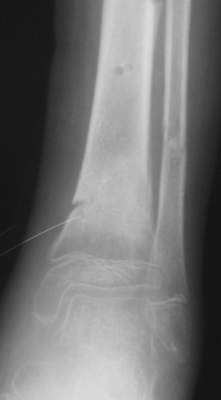

A> Это сросшийся перелом малоберцовой кости. И ложный сустав

A> н\3 б\берцовой кости.

Нашел в комп-ре схожий случай:

1) з/репозиция, 2) фиксация 2 спицами, 3) аппарат, 4) фиксационные

спицы удалены...